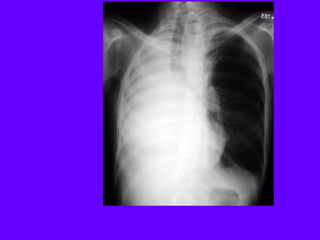

A 27-year-old man is referred to you for evaluation of an

abnormal chest radiograph. About 5 months ago, he consulted

a doctor because of excessive thirst. Evaluation resulted in the

diagnosis of diabetes insipidus, which responded favorably to

desmopressin administered nasally. Recently, he started to

notice shortness of breath when climbing stairs, and a chest

radiograph was obtained.

•Patient history reveals significant tobacco smoking, up to two

packs daily, for at least 14 years. The patient noticed the

shortness of breath for at least 2 years, and recently, he noted

a point of tenderness over the chest wall, lateral to the

posterior axillary line on the left.

•Oxygen saturation is 94% while breathing room air, and the

rest of his vital signs were normal. Auscultation reveals only

rare crackles without prolongation of the expiratory phase.

There is a point of tenderness over the left sixth and seventh

ribs in the posterior axillary line, and a chest CT scan is

obtained.